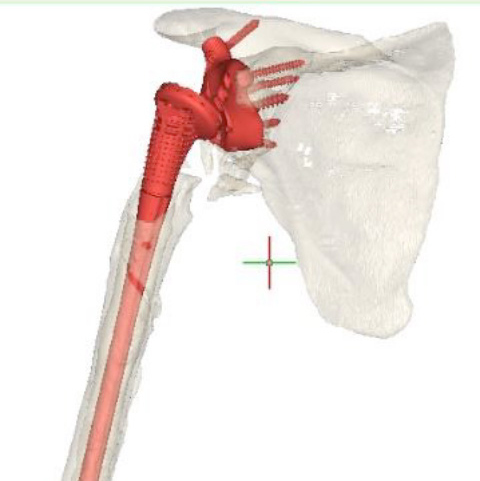

Post-op

Implants used:

- customLINK implant was a perfect fit

- Stable fixation of glenoid with seven bone screws

- Eccentric Glenosphere 42 mm / 4mm

- Modular Revision Stem, 75 mm length, size 24 mm

- Proximal Body, size L, height +5 mm

- Reverse Humeral Tray, neutral

- Reverse Humeral Insert, UHMWPE, dia. 42 mm, height 6 mm, 10° inclined

Final result:

- Good range of motion

- Good joint stability

- Good pain relief